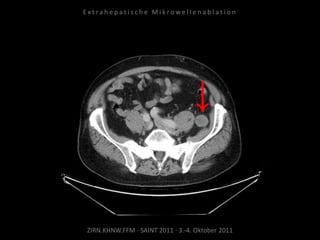

Bildgebung vor MWA:

CT vom 14.07.2010

Metastase lateral der linken Niere

nahe Colon descendens progredient.

Situation:

Metastasierung über längeren Zeitraum

lokal begrenzt,

1 Metastase progredient.

Organnahe Lage in unmittelbarer

Nachbarschaft zur linken Niere bzw. zum

Colon descendens.